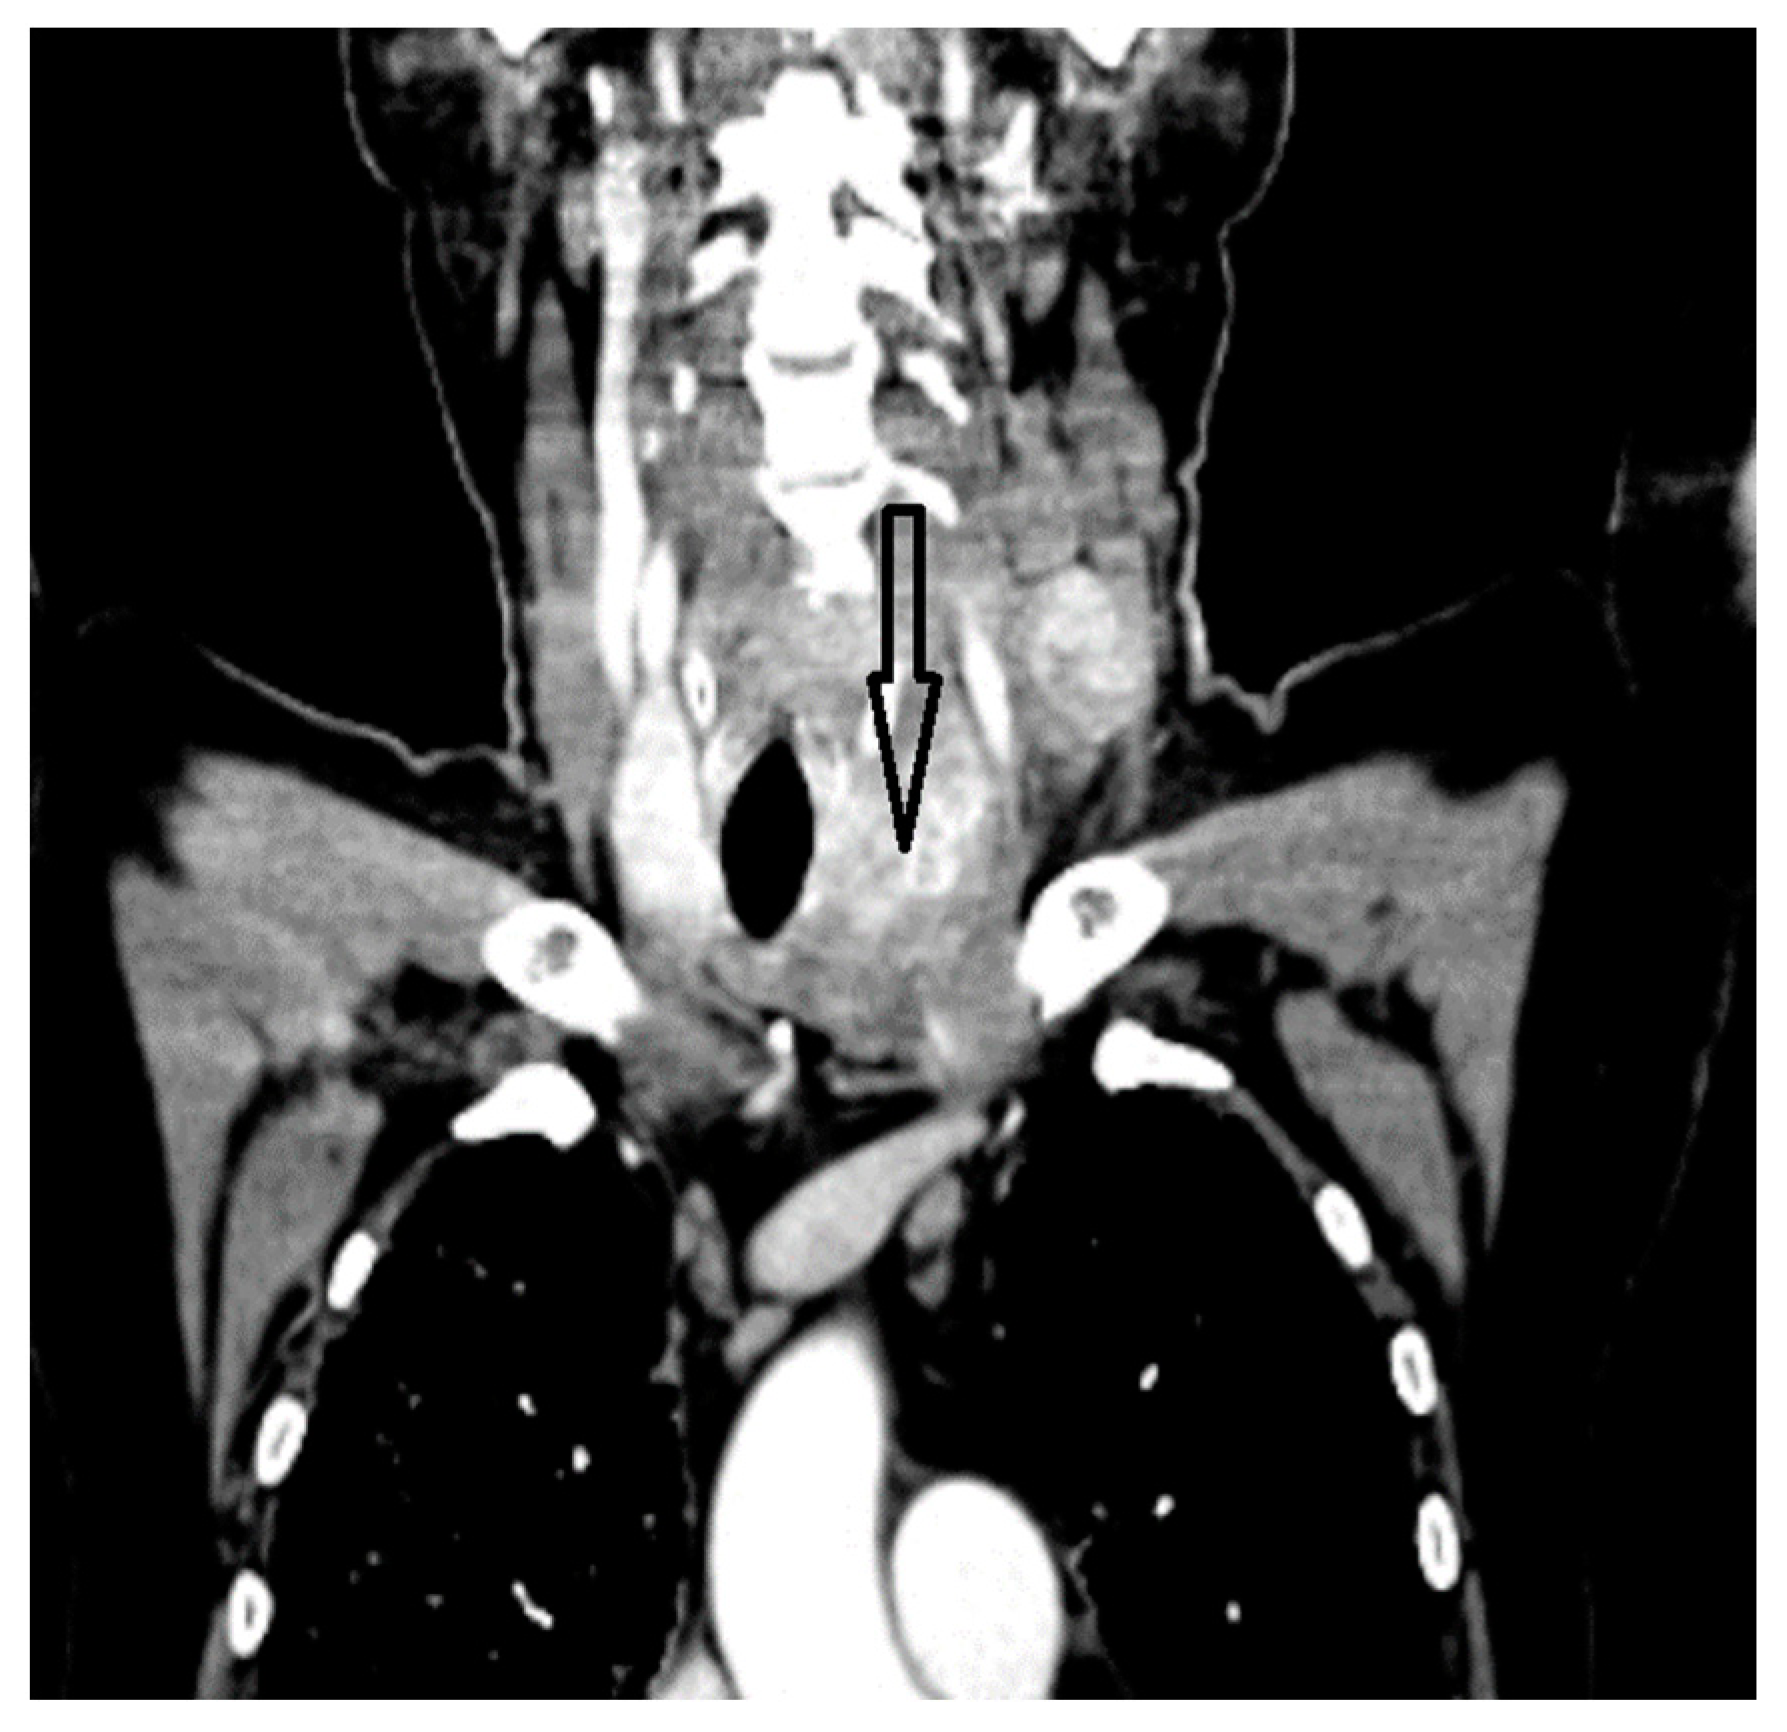

A whole-body contrast enhanced CT scan was subsequently performed, which demonstrated a 6/2.8 cm heterogeneous cervical mass that enclosed the left thyroid lobe and isthmus, as well as the posterior side of the sternocleidomastoid muscle (with no clear demarcation line), and superior extension to the larynx and to the thyroid cartilage. Inferiorly, invasion to the superior mediastinum structures was noted. Chest CT revealed multiple bilateral pulmonary nodules, suggestive of metastasis, and lymphangitic carcinomatosis. Several cervical and mediastinal lymph nodes with a tendency to confluate were also involved (Figure 1, Figure 2, Figure 3 and Figure 4).

Figure 1.

Thyroid mass comprising left lobe and isthmus.